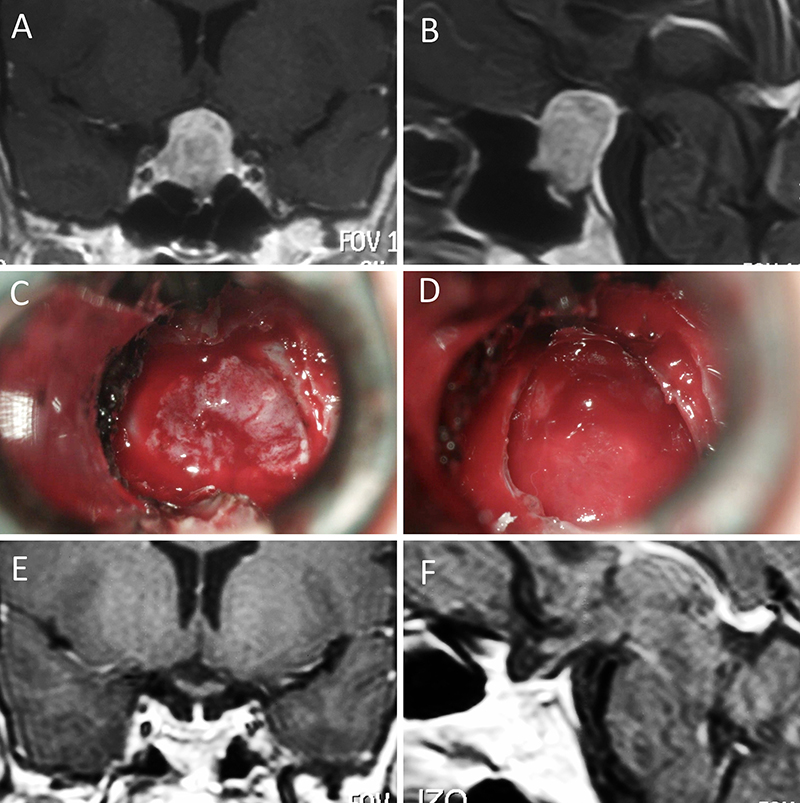

Figura 5: Apoplejía hipofisaria hemorrágica en un hombre de 32 años. El paciente presentó cefalea y parálisis completa del III par. Tuvo restitutio ad integrum en el seguimiento. A-B: RM preoperatoria; C-D: intraoperatorio; E-F: RM postoperatoria.

Figura 6: Apoplejía hipofisaria hemorrágica en un hombre de 55 años. El paciente presentó cefalea, déficit visual y parálisis completa del III par. Evolucionó favorablemente tras la cirugía, revirtiendo el cuadro. A-B: RM preoperatoria; C-D: intraoperatorio; E-F: RM postoperatoria.